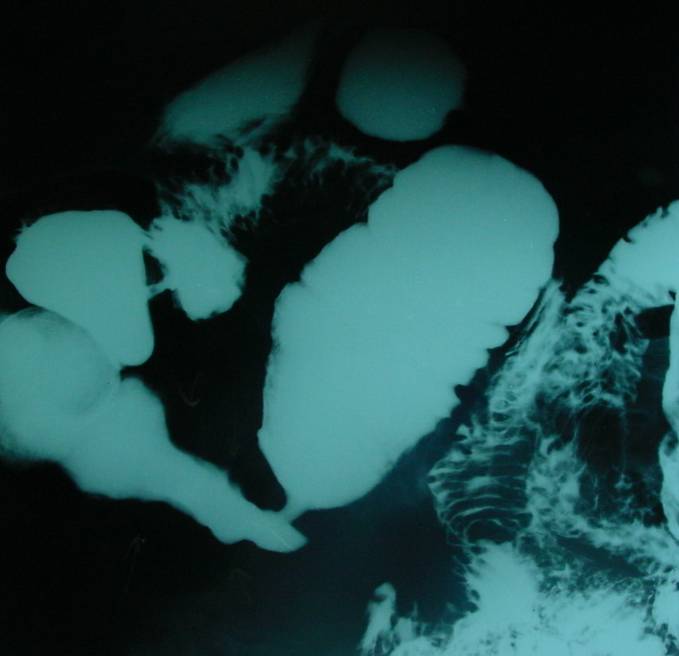

Konvansiyonel Radyoloji

• Kontrastlı grafilerde oral yolla verilen baryumun kontrast ajan olarak kullanılması ile ince barsak pasaj grafileri çekilir.

• Opak maddenin geçiş süresi

• Opak maddenin takılması

• Lümende olabilecek doluş defektleri

• Mukozal yapının daha iyi ortaya konabilmesi amacıyla “enteroclysis”.